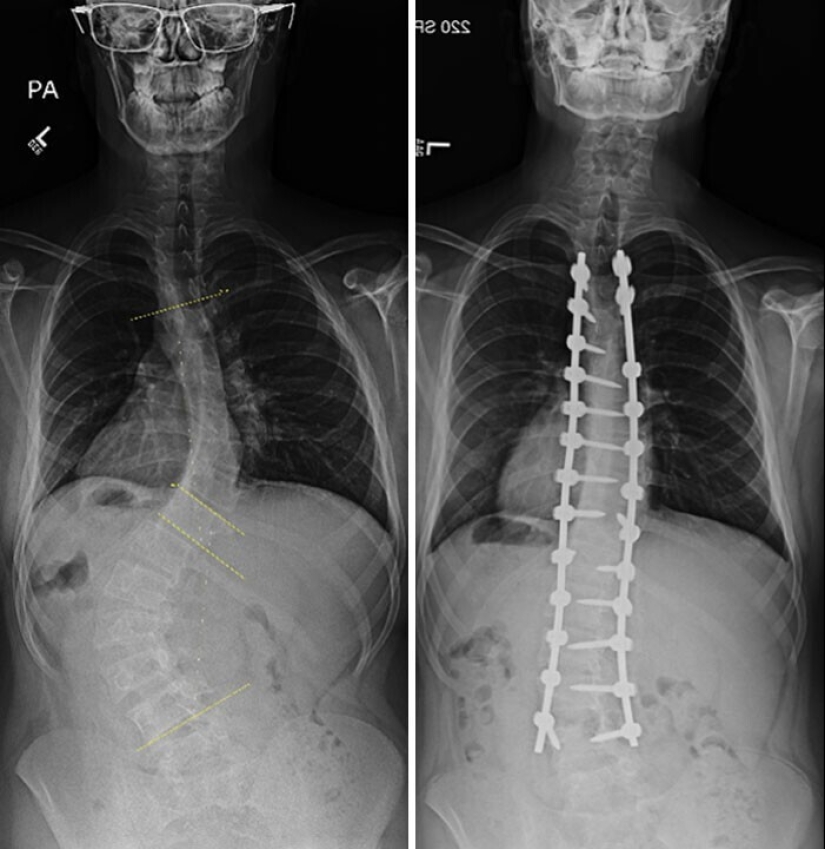

Operación sobre una curvatura de la columna vertebral antes y después de